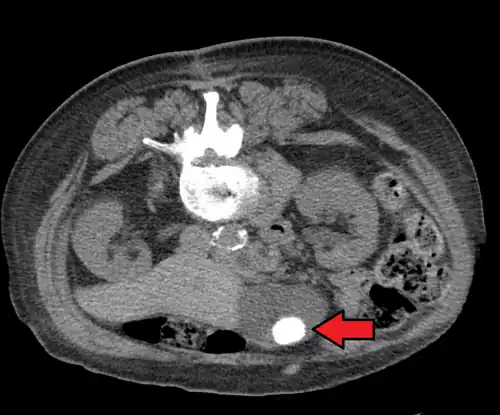

Gallstone ileus

Large gallstones can potentially erode through the gallbladder wall and into the neighboring small intestine. This large stone then travels through the small intestine until it is too narrow for the stone to continue, causing a small bowel obstruction. This obstruction often occurs at previous surgical sites or at the ileocecal valve (the portion of the bowel where the small intestine meets the large intestine). The patient presents with the inability to defecate or pass gas, nausea, vomiting, and severe abdominal pain.[14]